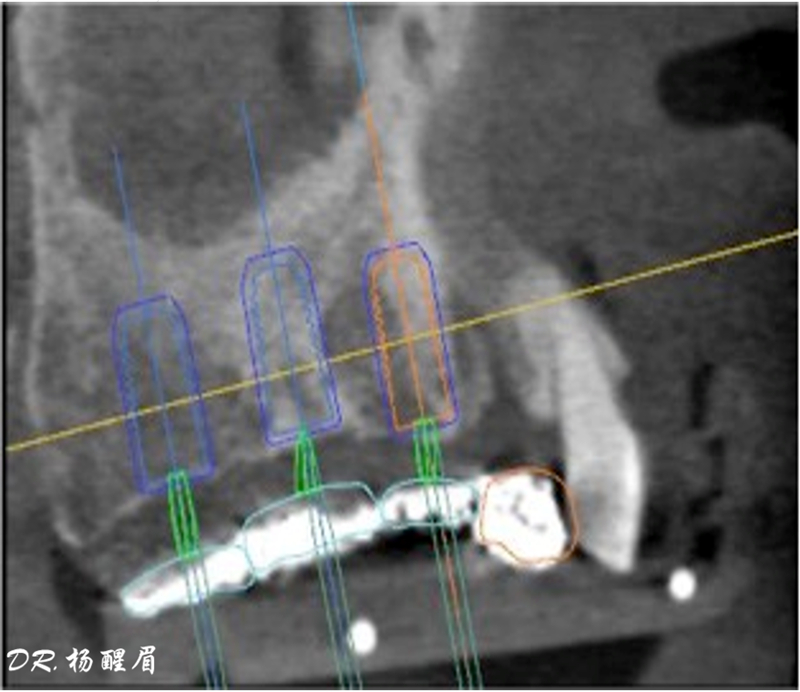

®按照術前方案進行備洞及植體植入

®按照術前方案進行備洞及植體植入,醫(yī)生可以通過屏幕軟件引導對手術中植入點、角度、深度實時追蹤

®對植體深度及方向進行確認

®完成3顆植體的植入,植體位點如術前方案設計,均在同軸線。